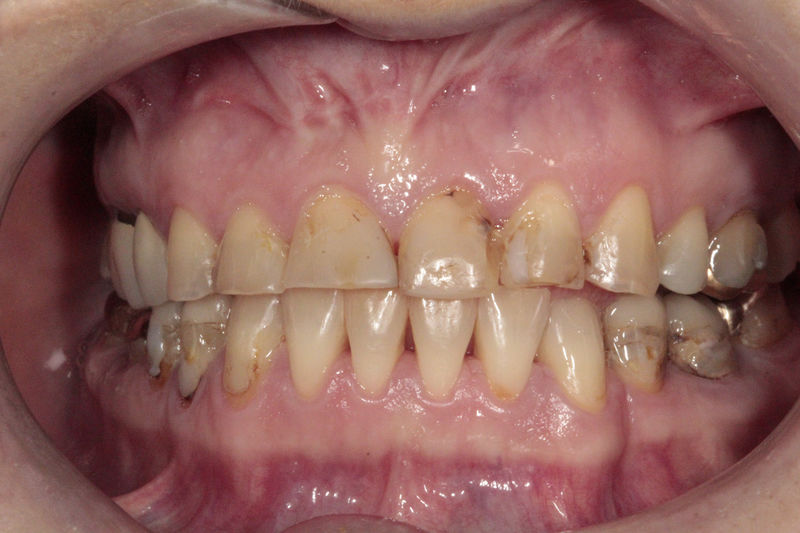

Disciplina fundamental de la Odontología enfocada en el diagnóstico, prevención y tratamiento restaurador de las piezas dentales que han sufrido daños. Su objetivo principal es devolver al diente su equilibrio biológico, funcional y estético cuando su integridad ha sido alterada. Resinas directas, incrustaciones, coronas.

Amplia gama de tratamientos para mejorar la apariencia de la sonrisa, corrigiendo el color, la forma, el tamaño, la alineación y la posición de los dientes. Los procedimientos más comunes y solicitados incluyen el blanqueamiento dental, las carillas y coronas, así como las resinas.

Implante fracasado, extracción, carillas, coronas y prótesis fija.

Implantes, ortodoncia y coronas.

Ortodoncia y coronas.

Cirugía ortognática, implantes, carillas y coronas,